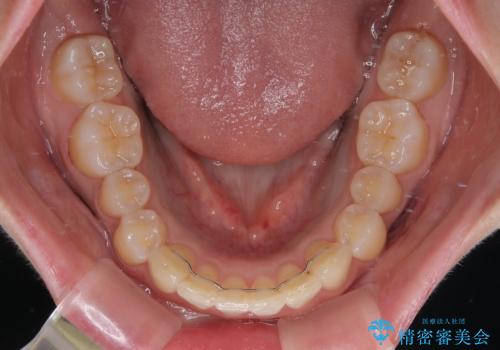

前歯の形が台形であり、歯列が整ったところでブラックトライアングルが目立つ仕上がりとなったため、IPR(歯と歯の間を削る処置)によって歯の形態を修正し、隙間の目立たない歯列に仕上げることができました。

上下左右の親知らずを抜歯し、上下ともに歯列を後方と側方に拡大し、口元を突出させることなくデコボコを解消することとしました。